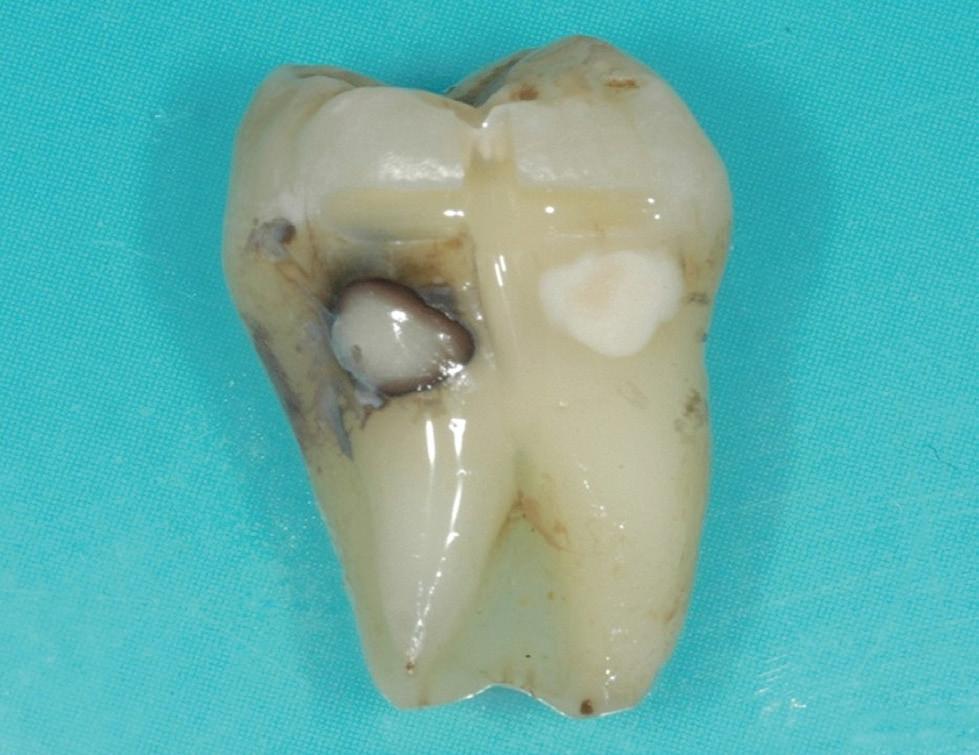

Estelite Asteria (Tokuyama)One of my favourite composite resin materials is Asteria which is a light-cured radiopaque composite for universal use. It considerably simplifies multilayer techniques yet delivers outstanding aesthetics with excellent polishability. Unlike mul tilayer techniques used with conventional composites, Asteria uses only 2 layers for optimal results without compromising aesthetics. The microstructure of the material produces a light diffusion that helps blend in with the natural tooth structure. The chameleon like nature of the material allows a blending of the materials to natural tooth structure and it allows excellent polishability which retains its lustre over time.